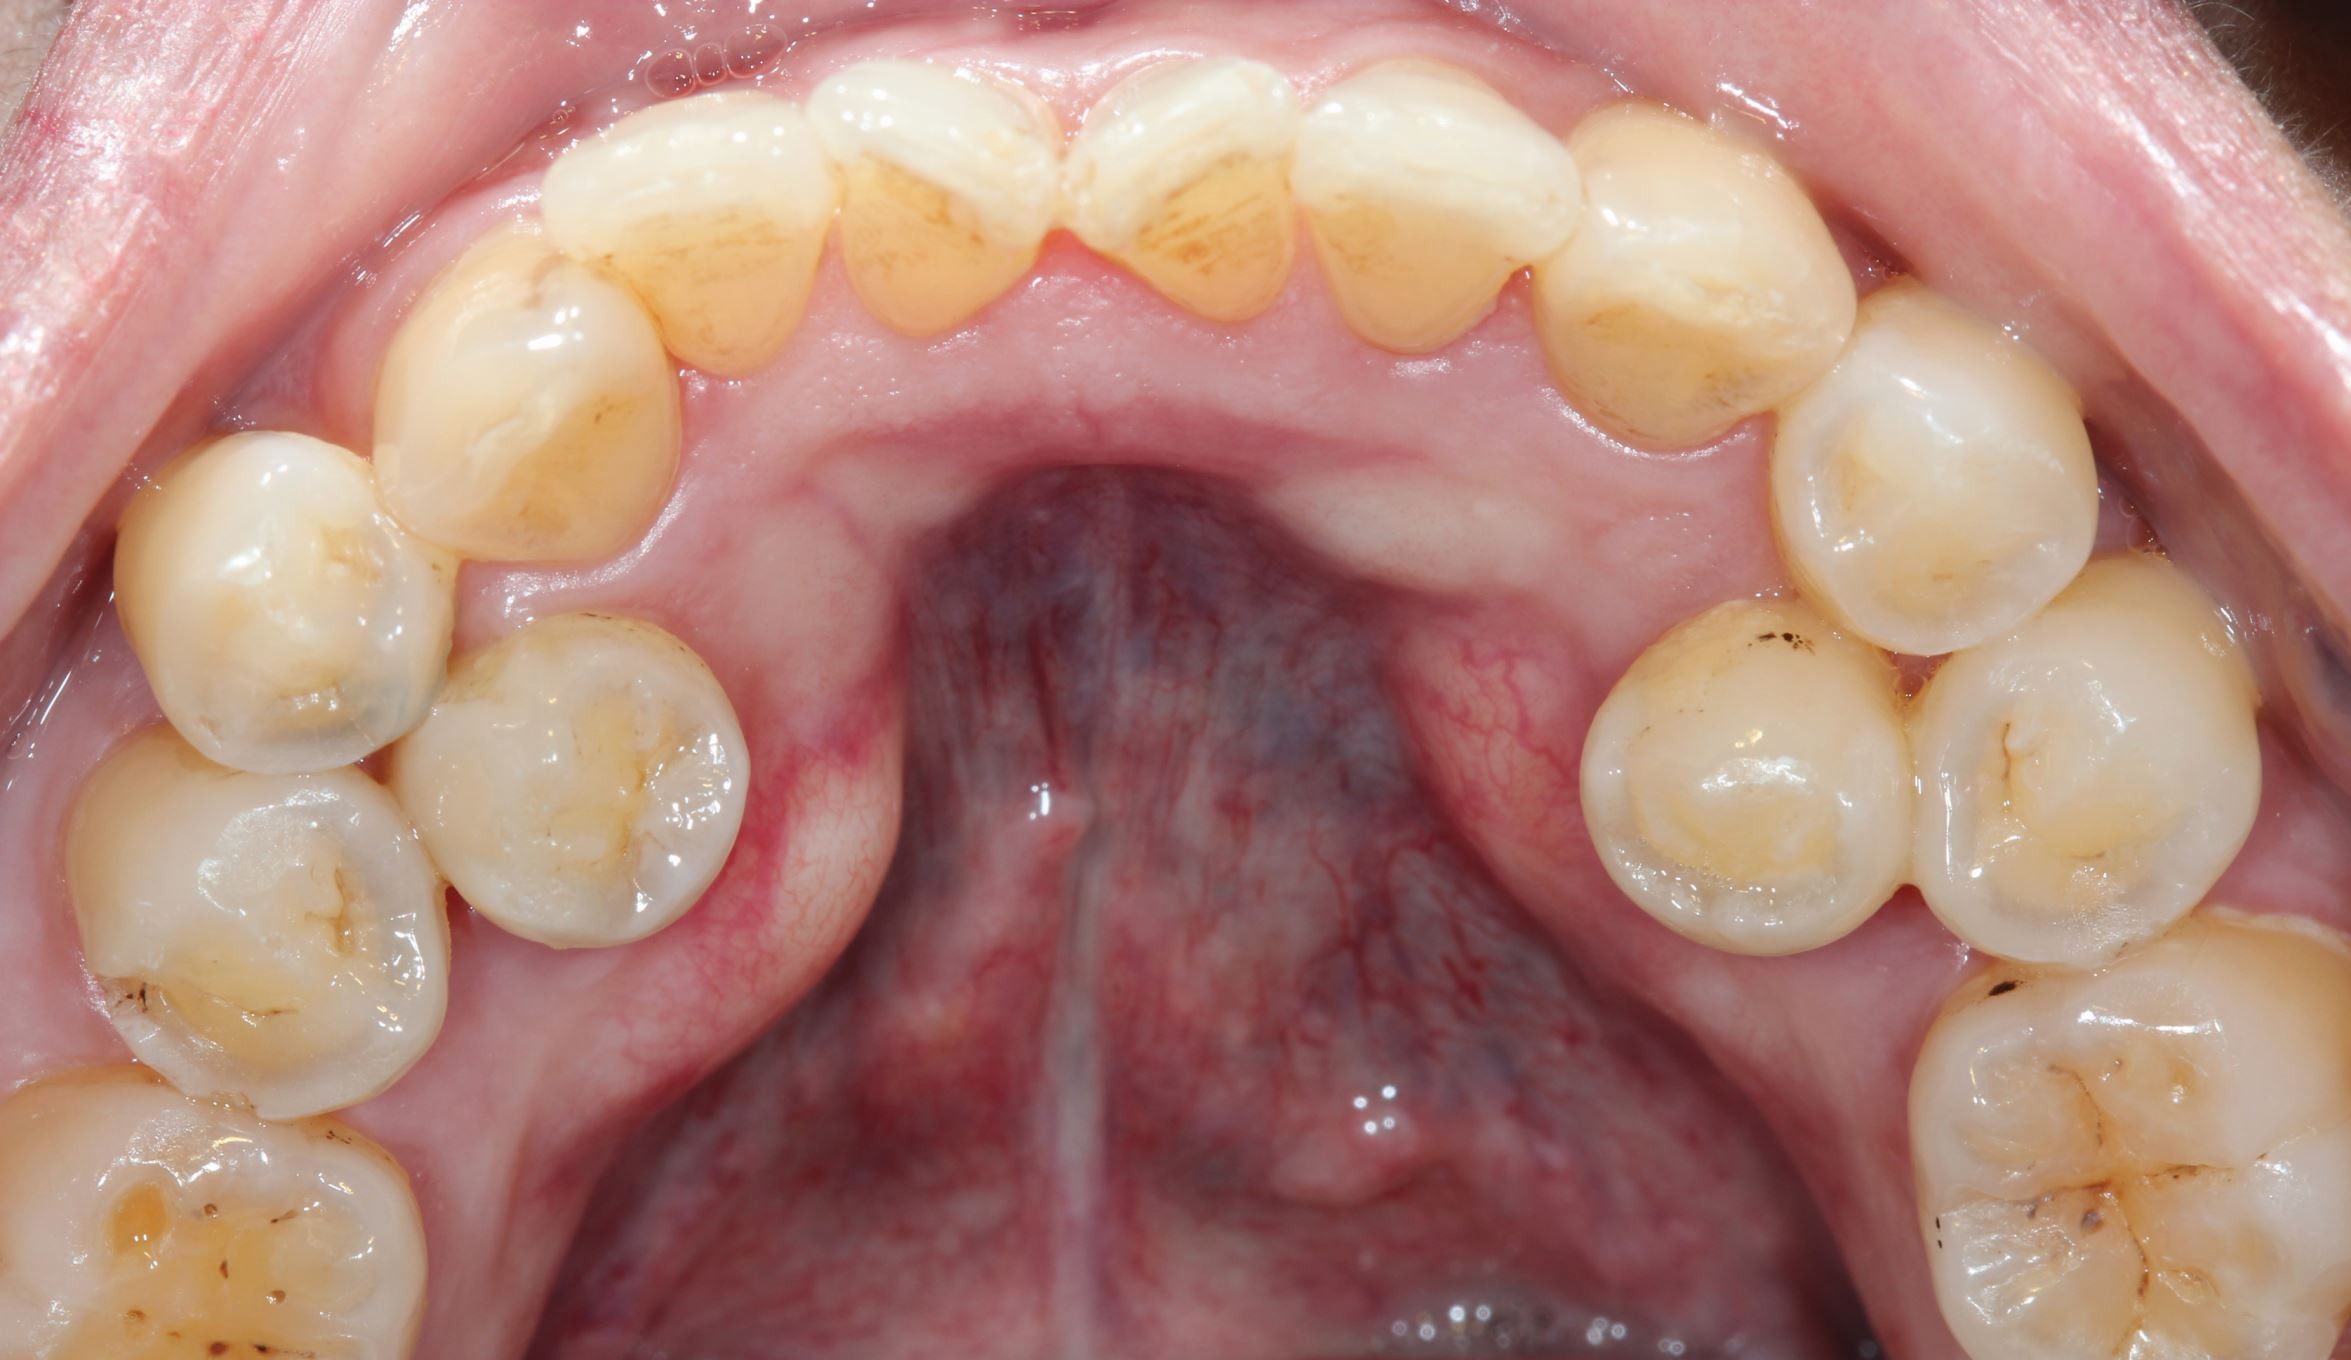

Familial multiple impacted supernumerary teeth: Case report - Loulwah K Alothman, Azizah F Bin Mubayrik, Reema Alshawaf, Randa Alfotawi, Abdulaziz S Alqahtani, 2025

image size: 1058x1200